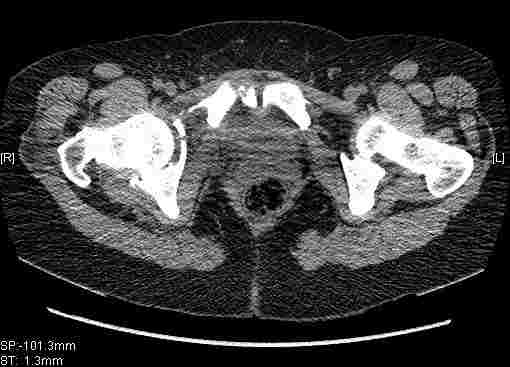

Re: Т-образный перелом вертлужной впадины

Удалось сегодня вывести пациентку в соседнюю больницу, где есть кт. Срезы сделаны только горизонтальные.